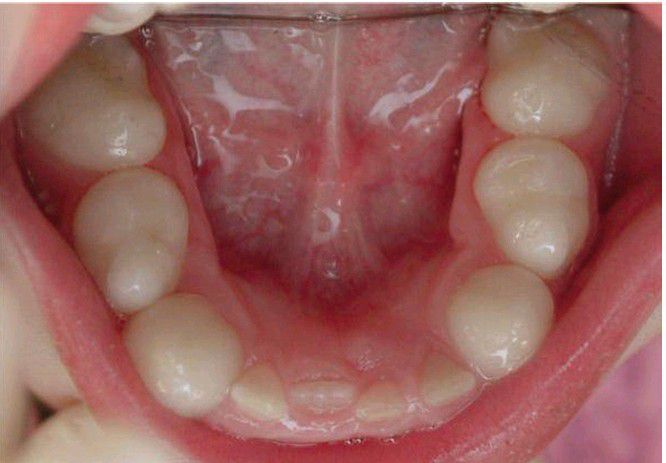

Globodontia

Dentition demonstrating clinically normal anterior teeth and posterior teeth with enlarged bulbous crowns. Patient had undiagnosed hearing loss that was discovered following identification of otodental syndrome by dentist.